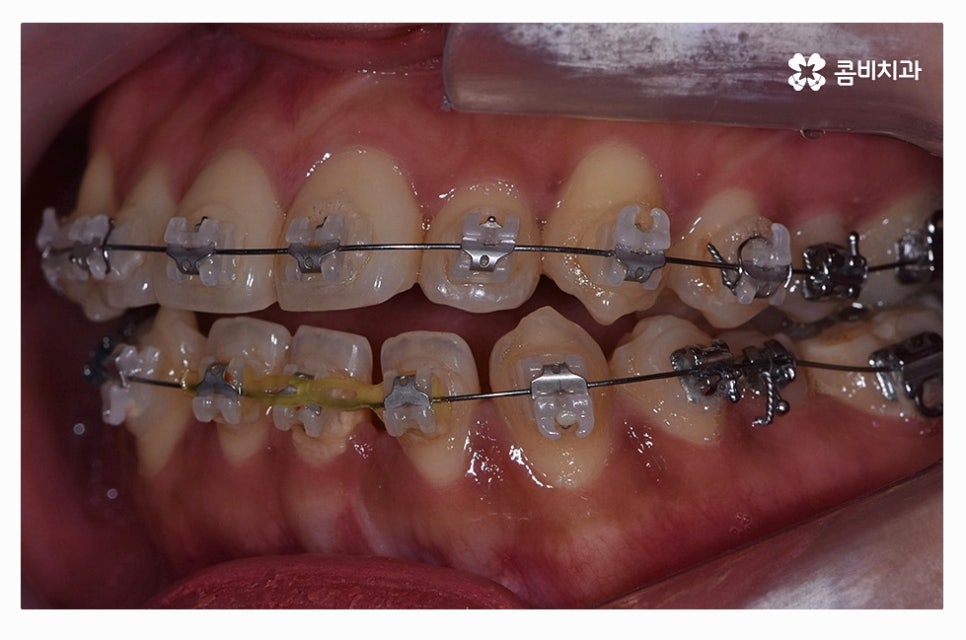

치아교정은 장기간의 치료 계획을 세워야 하기 때문에

교정 효율성이 좋고, 상대적으로 통증이 적으며 관리가 편리한

클리피씨 장치가 보편적으로 많이 활용되고 있으며

치열 상태나 환자의 니즈에 따라서 심미성이 높은 설측교정이나

투명교정이 활용되는 경우도 있어요.